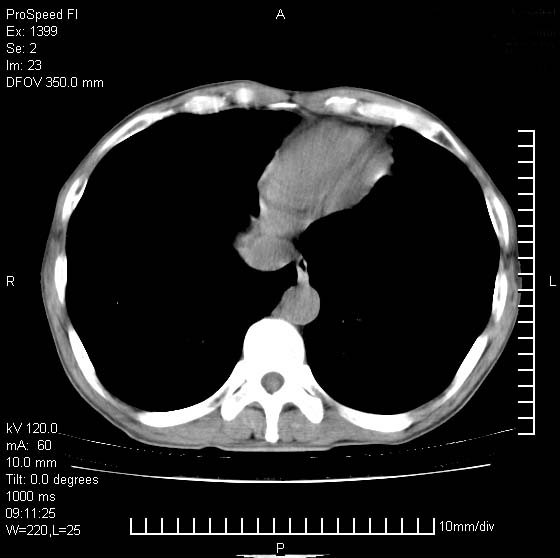

以下是引用rgsyyf在2007-1-19 11:05:00的发言:[br]左肺上叶见形态不规则巨大软组织肿块影,边缘呈分叶征,纵隔内隆突下见肿大淋巴结,右肺内另见一不规则结节影 .考虑:左肺周围性肺癌伴纵隔即右肺内转移.